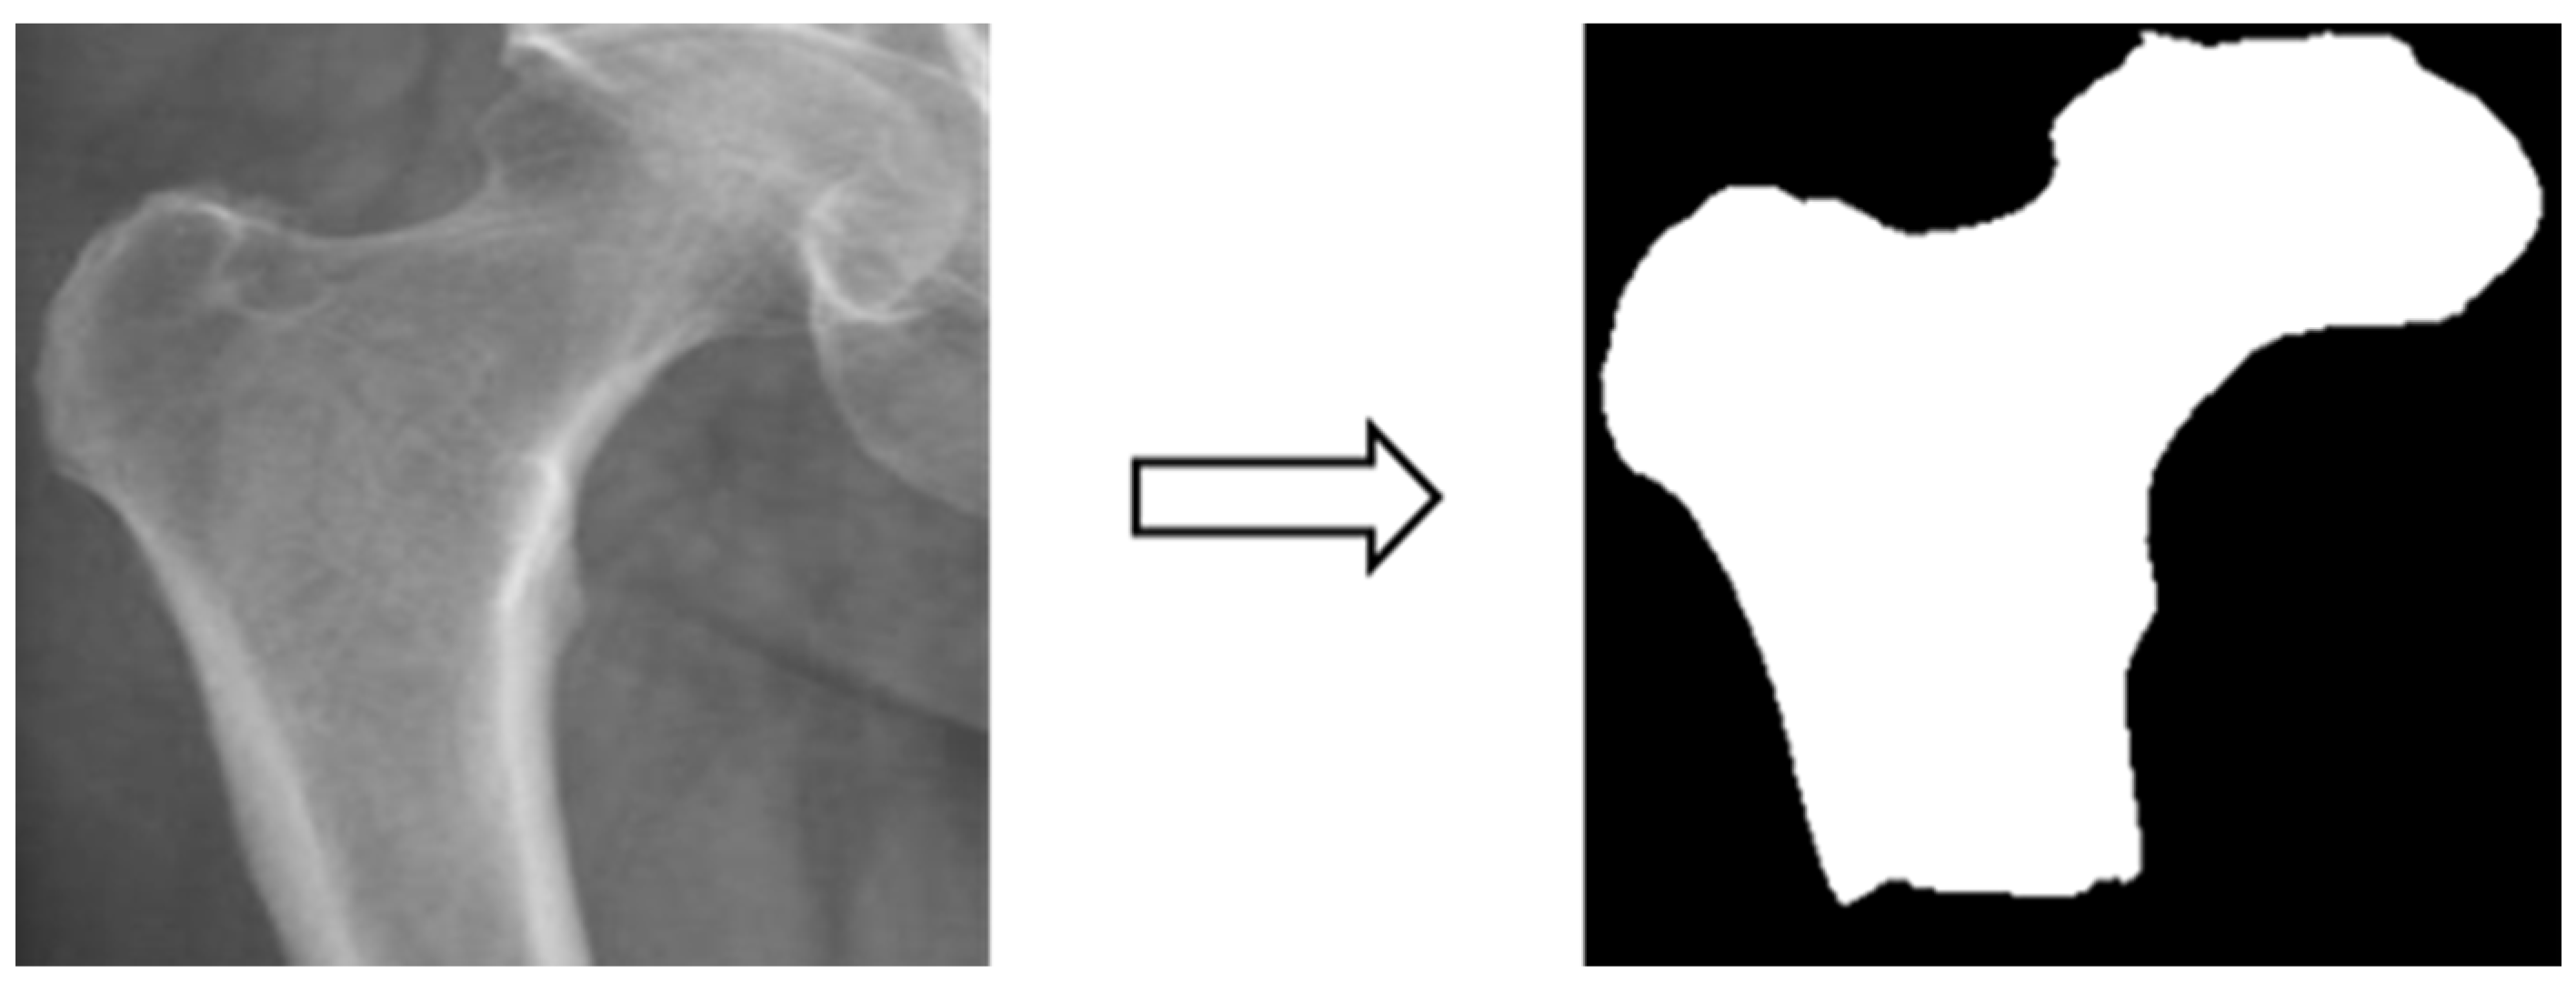

3.3.1. Image Labeling

In this study, X-ray images of each of the four areas of the patient’s hip (femoral neck, greater trochanter, Ward’s triangle, and total hip) were separated and manually labeled using Labelme, an open-source tool that can be used for labeling [29]. The four parts of the hip were then framed as shown in Figure 2 below, and the labeled image data were batch converted into binary png files, which were used as inputs for the supervised learning training of U-Net, U-Net++, and image categorization in the image segmentation process.

3.3.2. Image Segmentation